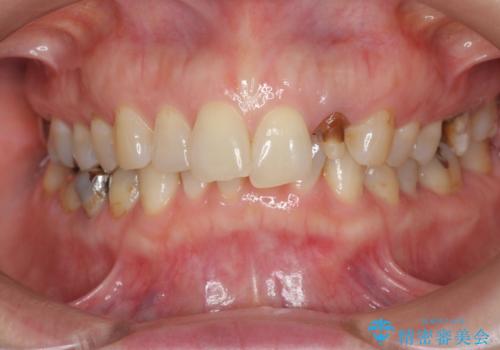

口腔内をメタルフリーにしたい

- 「 銀歯が原因で皮膚にアレルギー症状が出ている。」、と皮膚科のかかりつけ医に言われメタルフリー治療を希望され来院されました。

拡大鏡下で丁寧に銀歯の除去を行ったのち、金属を用いないセラミックインレー・クラウンによる治療を行います。